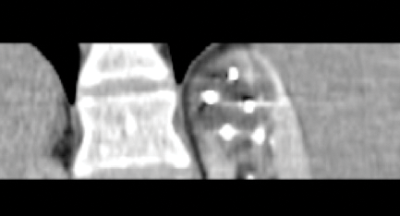

Once the probes are appropriately positioned it may be necessary to protect vulnerable adjacent structures, such as the bowel, pancreas or ureter. The adjunctive techniques most commonly employed to achieve this protection involve the injection of fluid (hydrodissection) or gas (air dissection) to displace at risk structures (Figure 3).

Figure 3: Peri-treatment image depicting cryoprobes within the iceball

and a protective layer of contrast tinted hydrodissection.